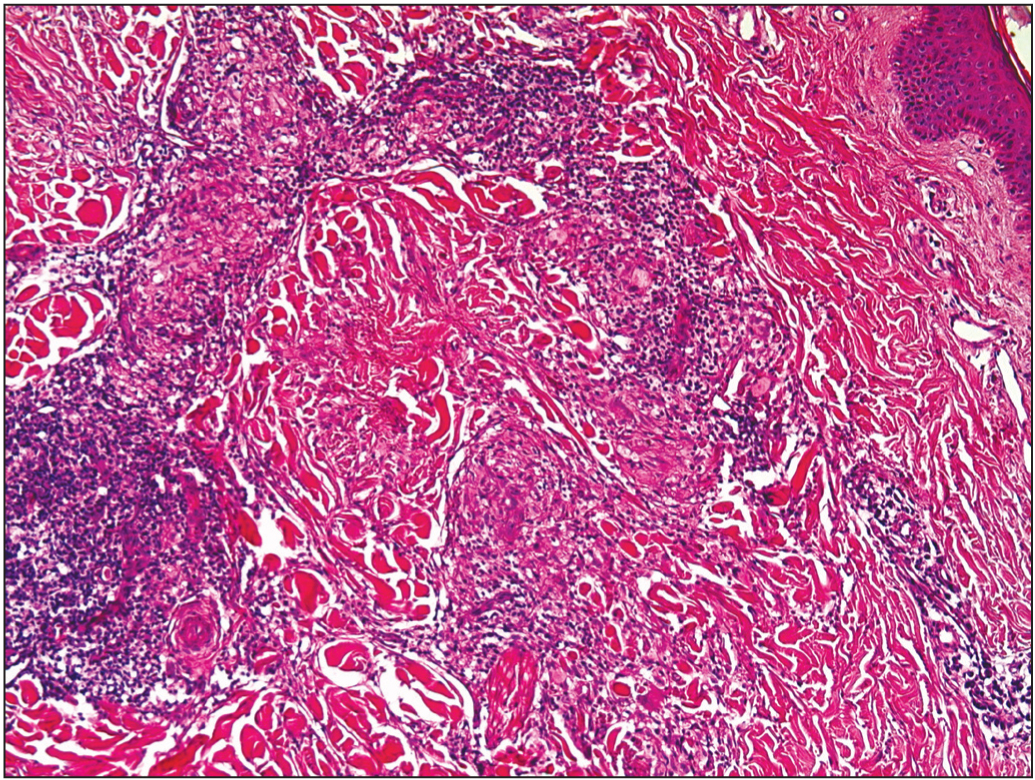

Гистологически основная область некробиоза коллагена располагается в нижних отделах дермы; вокруг нее наблюдается инфильтрат, состоящий из фибробластов, лимфоидных клеток и гистиоцитов (рис. 3). При окраске Суданом III обнаруживается характерное внеклеточное отложение липидов (рис. 4), а при окраске толуидиновым синим возможно выявление муцина [24].

Рис. 3. Гистологический препарат. Лимфогистиоцитарный инфильтрат вокруг области некробиоза коллагена.

Рис. 4. Гистологический препарат. Внеклеточное отложение липидов.